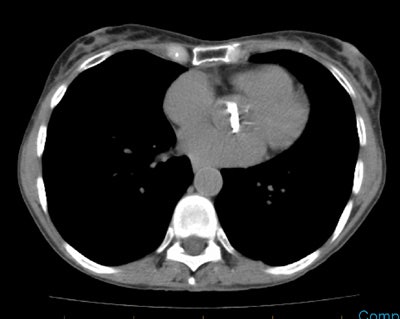

Case 2: Heavily calcified aortic valve

The lateral CXR below revealed dense calcifications in the region of the aortic valve (black arrows). When seen on plain film, the findings is very suggestive of aortic stenosis. CT imaging in this same patient also revealed very dense aortic valve calcifications.